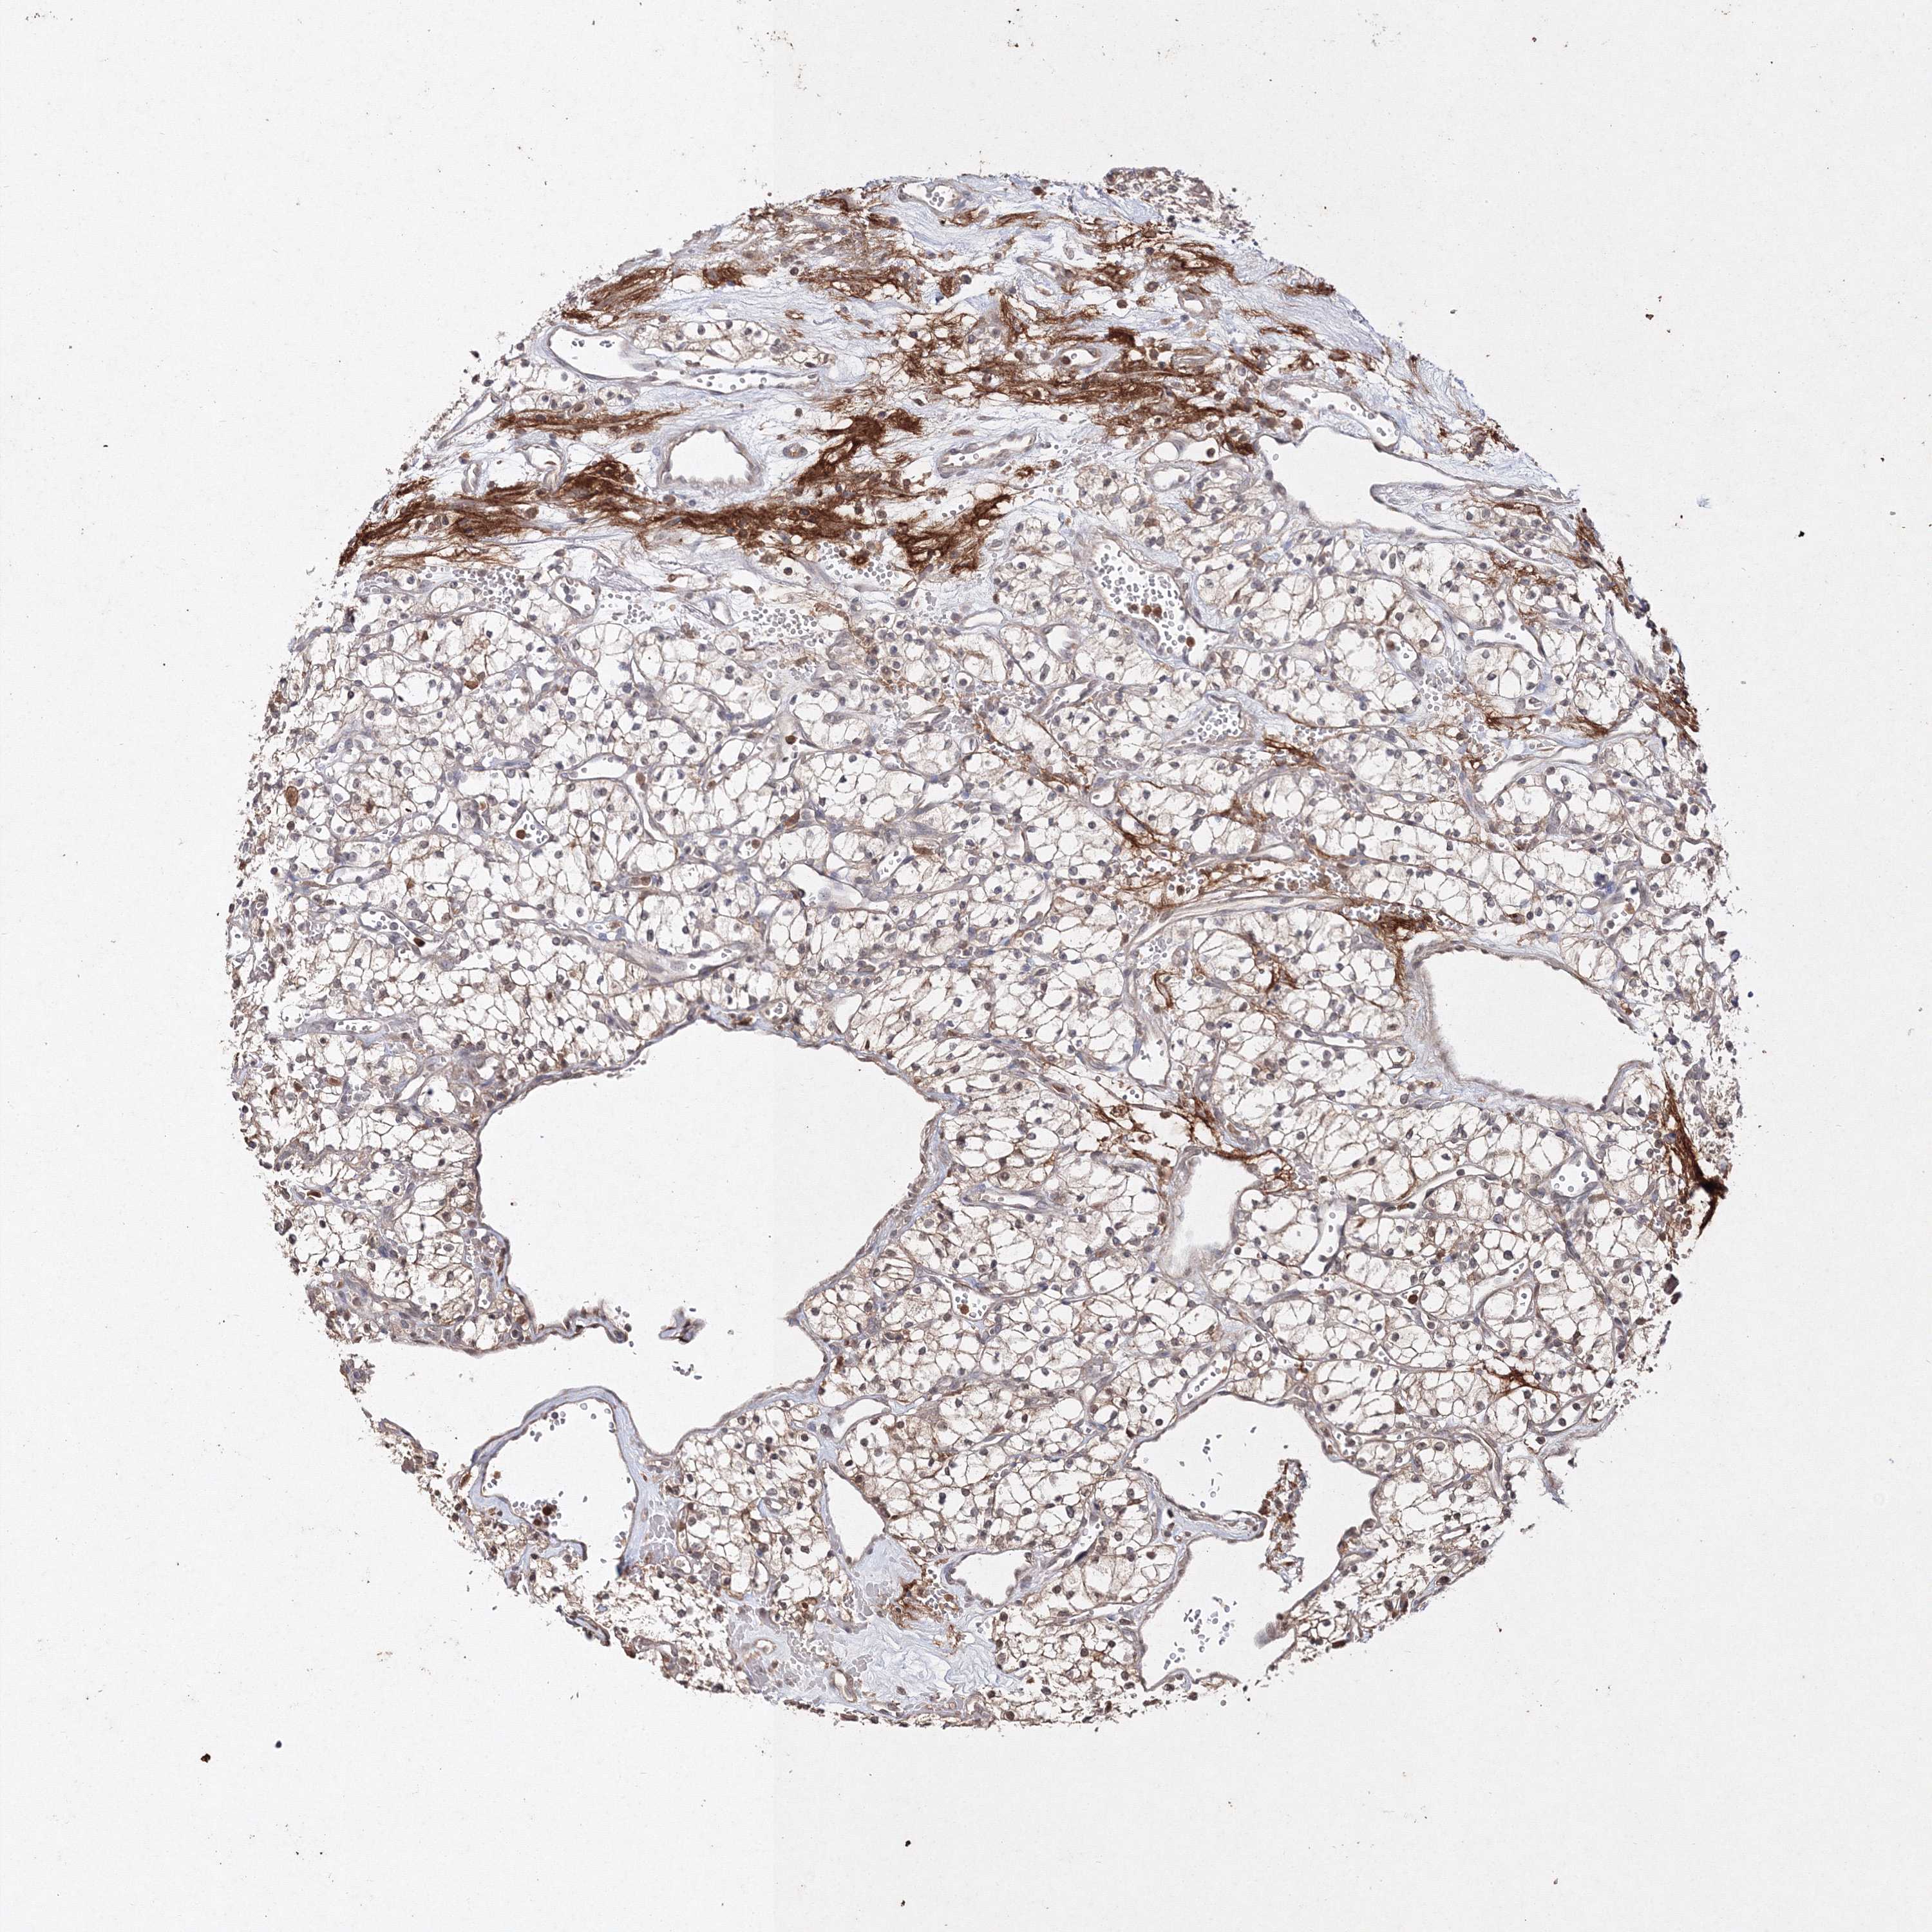

S100A11 is validated prognostic, high expression is unfavorable in Kidney Renal Clear Cell Carcinoma (validation)

Best expression cut offi

Based on the FPKM value of each gene, patients were classified into two groups and association between prognosis (survival) and gene expression (FPKM) was examined. The best expression cut-off refers the FPKM value that yields maximal difference with regard to survival between the two groups at the lowest log-rank P-value. Best expression cut-off was selected based on survival analysis .

When clicking on this number, the vertical dashed line indicating cut-off, the interactive survival plot, and the Kaplan-Meier curve will be adjusted to show results based on the best expression cut-off.

: 987.74

TCGA RNA samplesi

RNA-seq data is reported as average FPKM (number Fragments Per Kilobase of exon per Million reads), generated by the The Cancer Genome Atlas (TCGA) .

Normal distribution across the dataset is visualized with box plots, shown as median and 25th and 75th percentiles. Points are displayed as outliers if they are above or below 1.5 times the interquartile range. FPKM values of the individual samples are presented next to the box plot.

Average pTPM 833.5

Number of samples 100